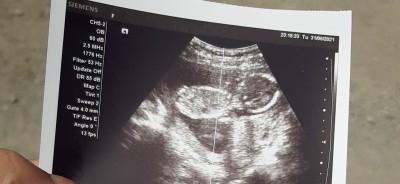

Kızlar bu önce ki ultrason yüzünü kapattığını demişti  bacağını erkeğe benziyo dediler ama net değil diyolar erkek mi sizce

Gebelik haftası 20+2